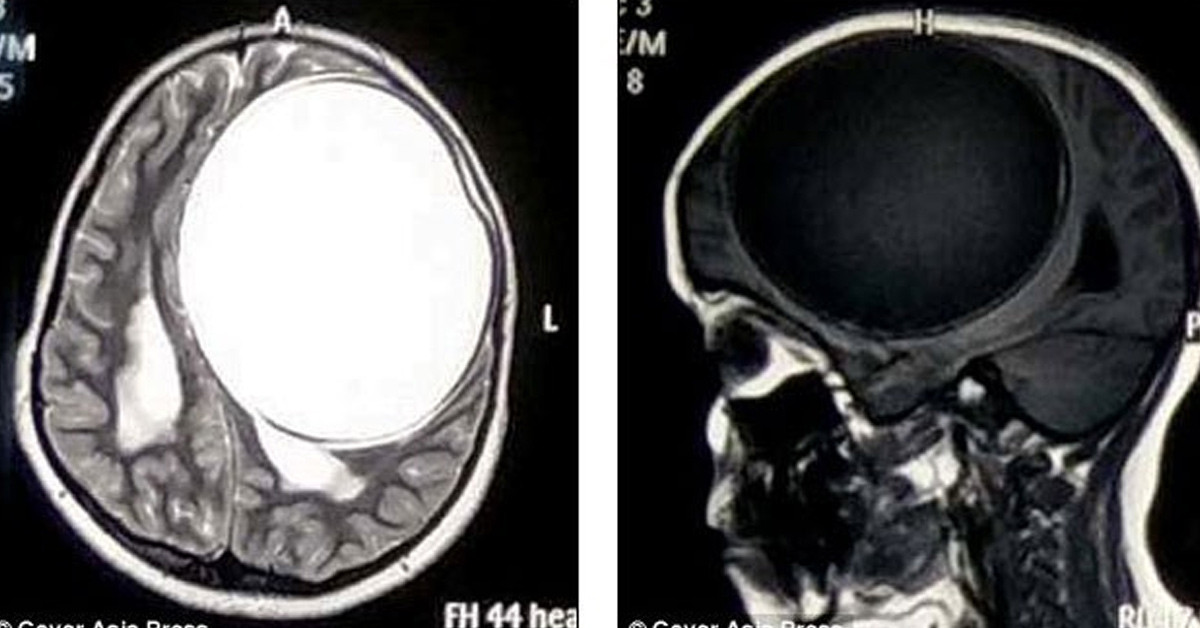

12 yaşındaki Hintli Nita Juggi sürekli nöbet geçiriyor ve son 12 aydır vücudunun bir tarafı felçli haldeydi. Doktora başvurduktan sonra yapılan çeşitli tetkikler sonrasında küçük kızın beyninin yarısını kaplayan Tenya yani bağırsak kurdu larvalarından kaynaklı merkezi sinir sisteminde Sistiserkoz teşhis edildi.

Bir bağırsak kurdunun larvasının sebep olduğu kist greyfurt büyüklüğünde ve her an patlayıp ölüme sebep olabilecek boyutlardaydı. başarılı bir ameliyatla beynindeki kist alınan kız şuan iyileşme sürecinde. Tenya olarak da bilinen bağırsak kurtları parazit bir hayat sürer ve yetişkinlik döneminde bağırsaklarda yaşayarak inanılmaz boyutlara ulaşabilirler. yetişkinlikten önce büyük kistler içerinde bulunan larvalar beyne ulaşabilir ve burada büyümeye devam edebilir.